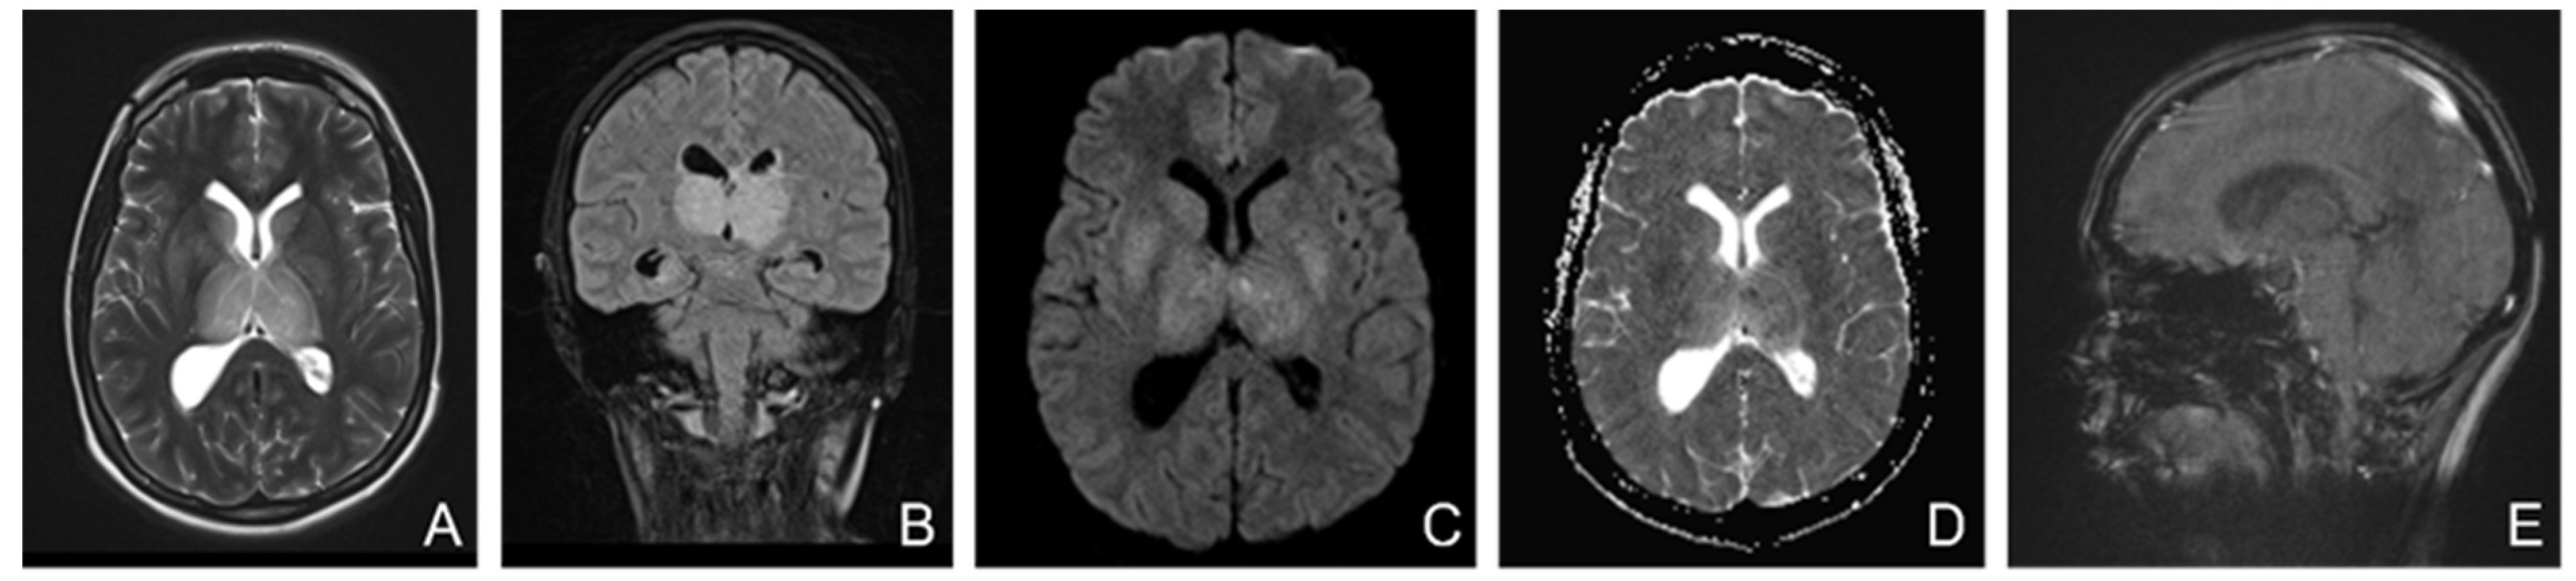

A brain MRI (Figure 5) showed flow asymmetry at the level of the cavernous sinuses, left more than right, coupled with fluid accumulation in the left mastoid cells, whilst cerebral parenchyma had morphology and signals within normal limits, thus establishing the diagnosis of bilateral (left > right) cavernous sinus thrombosis. The patient was started on continuous heparin infusion followed by treatment with acenocoumarol.

Figure 5.

Non-enhanced MRI (at onset): ((A)—T2 axial, (B)—T1 sagittal, (C)—T2* axial, (D)—venous TOF coronal) shows unremarkable parenchyma and absence of flow in cavernous sinuses on TOF imagesFive months later, the patient came back to our clinic complaining of paroxysmal episodes of altered state of consciousness with language disorders such as verbal barrage followed by disorientation. An EEG was performed, showing a low-voltage background path, weakly modulated in spindles in the left derivations, reactive when opening the eyes, and rare isolated degraded peak-wave complexes, thus concluding that the patient was experiencing focal onset impaired awareness seizures; she was then started on antiepileptic treatment with oxcarbazepine 300 mg twice daily. She also was psychiatrically examined due to emotional lability confirming the diagnosis of depression and allowing antidepressant treatment to be started.